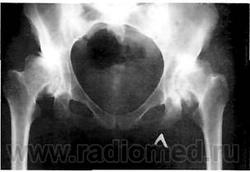

Рис. 8. Рентгенограмма больного с двухсторонним диспластическим коксартрозом III ст. Деформация и подвывих головок бедренных костей, резкое сужение суставных щелей, остеофиты нижних полюсов вертлужных впадин и головок бедренных костей, остеосклероз нагружаемых отделов крыши вертлужной впадины.

При дальнейшей нагрузке происходит постепенная деформация головки бедренной кости; она смещается вверх, ротируется кнаружи и приводится, что клинически соответствует развитию стойкой сгибательно-приводящей контрактуры сустава (рис. 8).

Мы в своей практике пользуемся классификацией Crowe, в основу которой положена степень смещения головки бедренной кости относительно вертлужной впадины: 1 степень - нижний край головки смещен вверх относительно нижнего края ВВ на 50% размера самой головки; 2 степень - смещение головки составляет 50 - 75%; 3 степень - 75 - 100% и 4 степень - более 100%. Отличительной особенностью анатомического строения ВВ при 3-4 степени дисплазии (к ранее перечисленным) является недоразвитие ВВ, которая имеет треугольную форму и малые размеры.